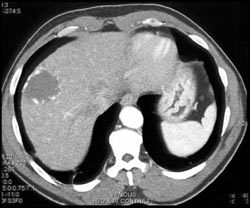

Hemangioma